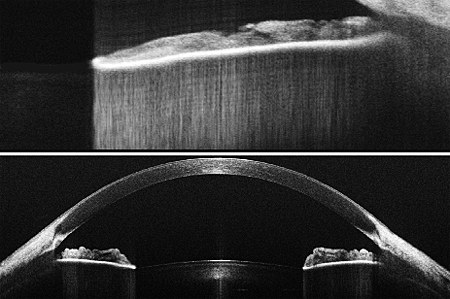

Wasatch Photonics' 1300nm OCT solutions suit dermatology, anterior segment imaging and material inspection.